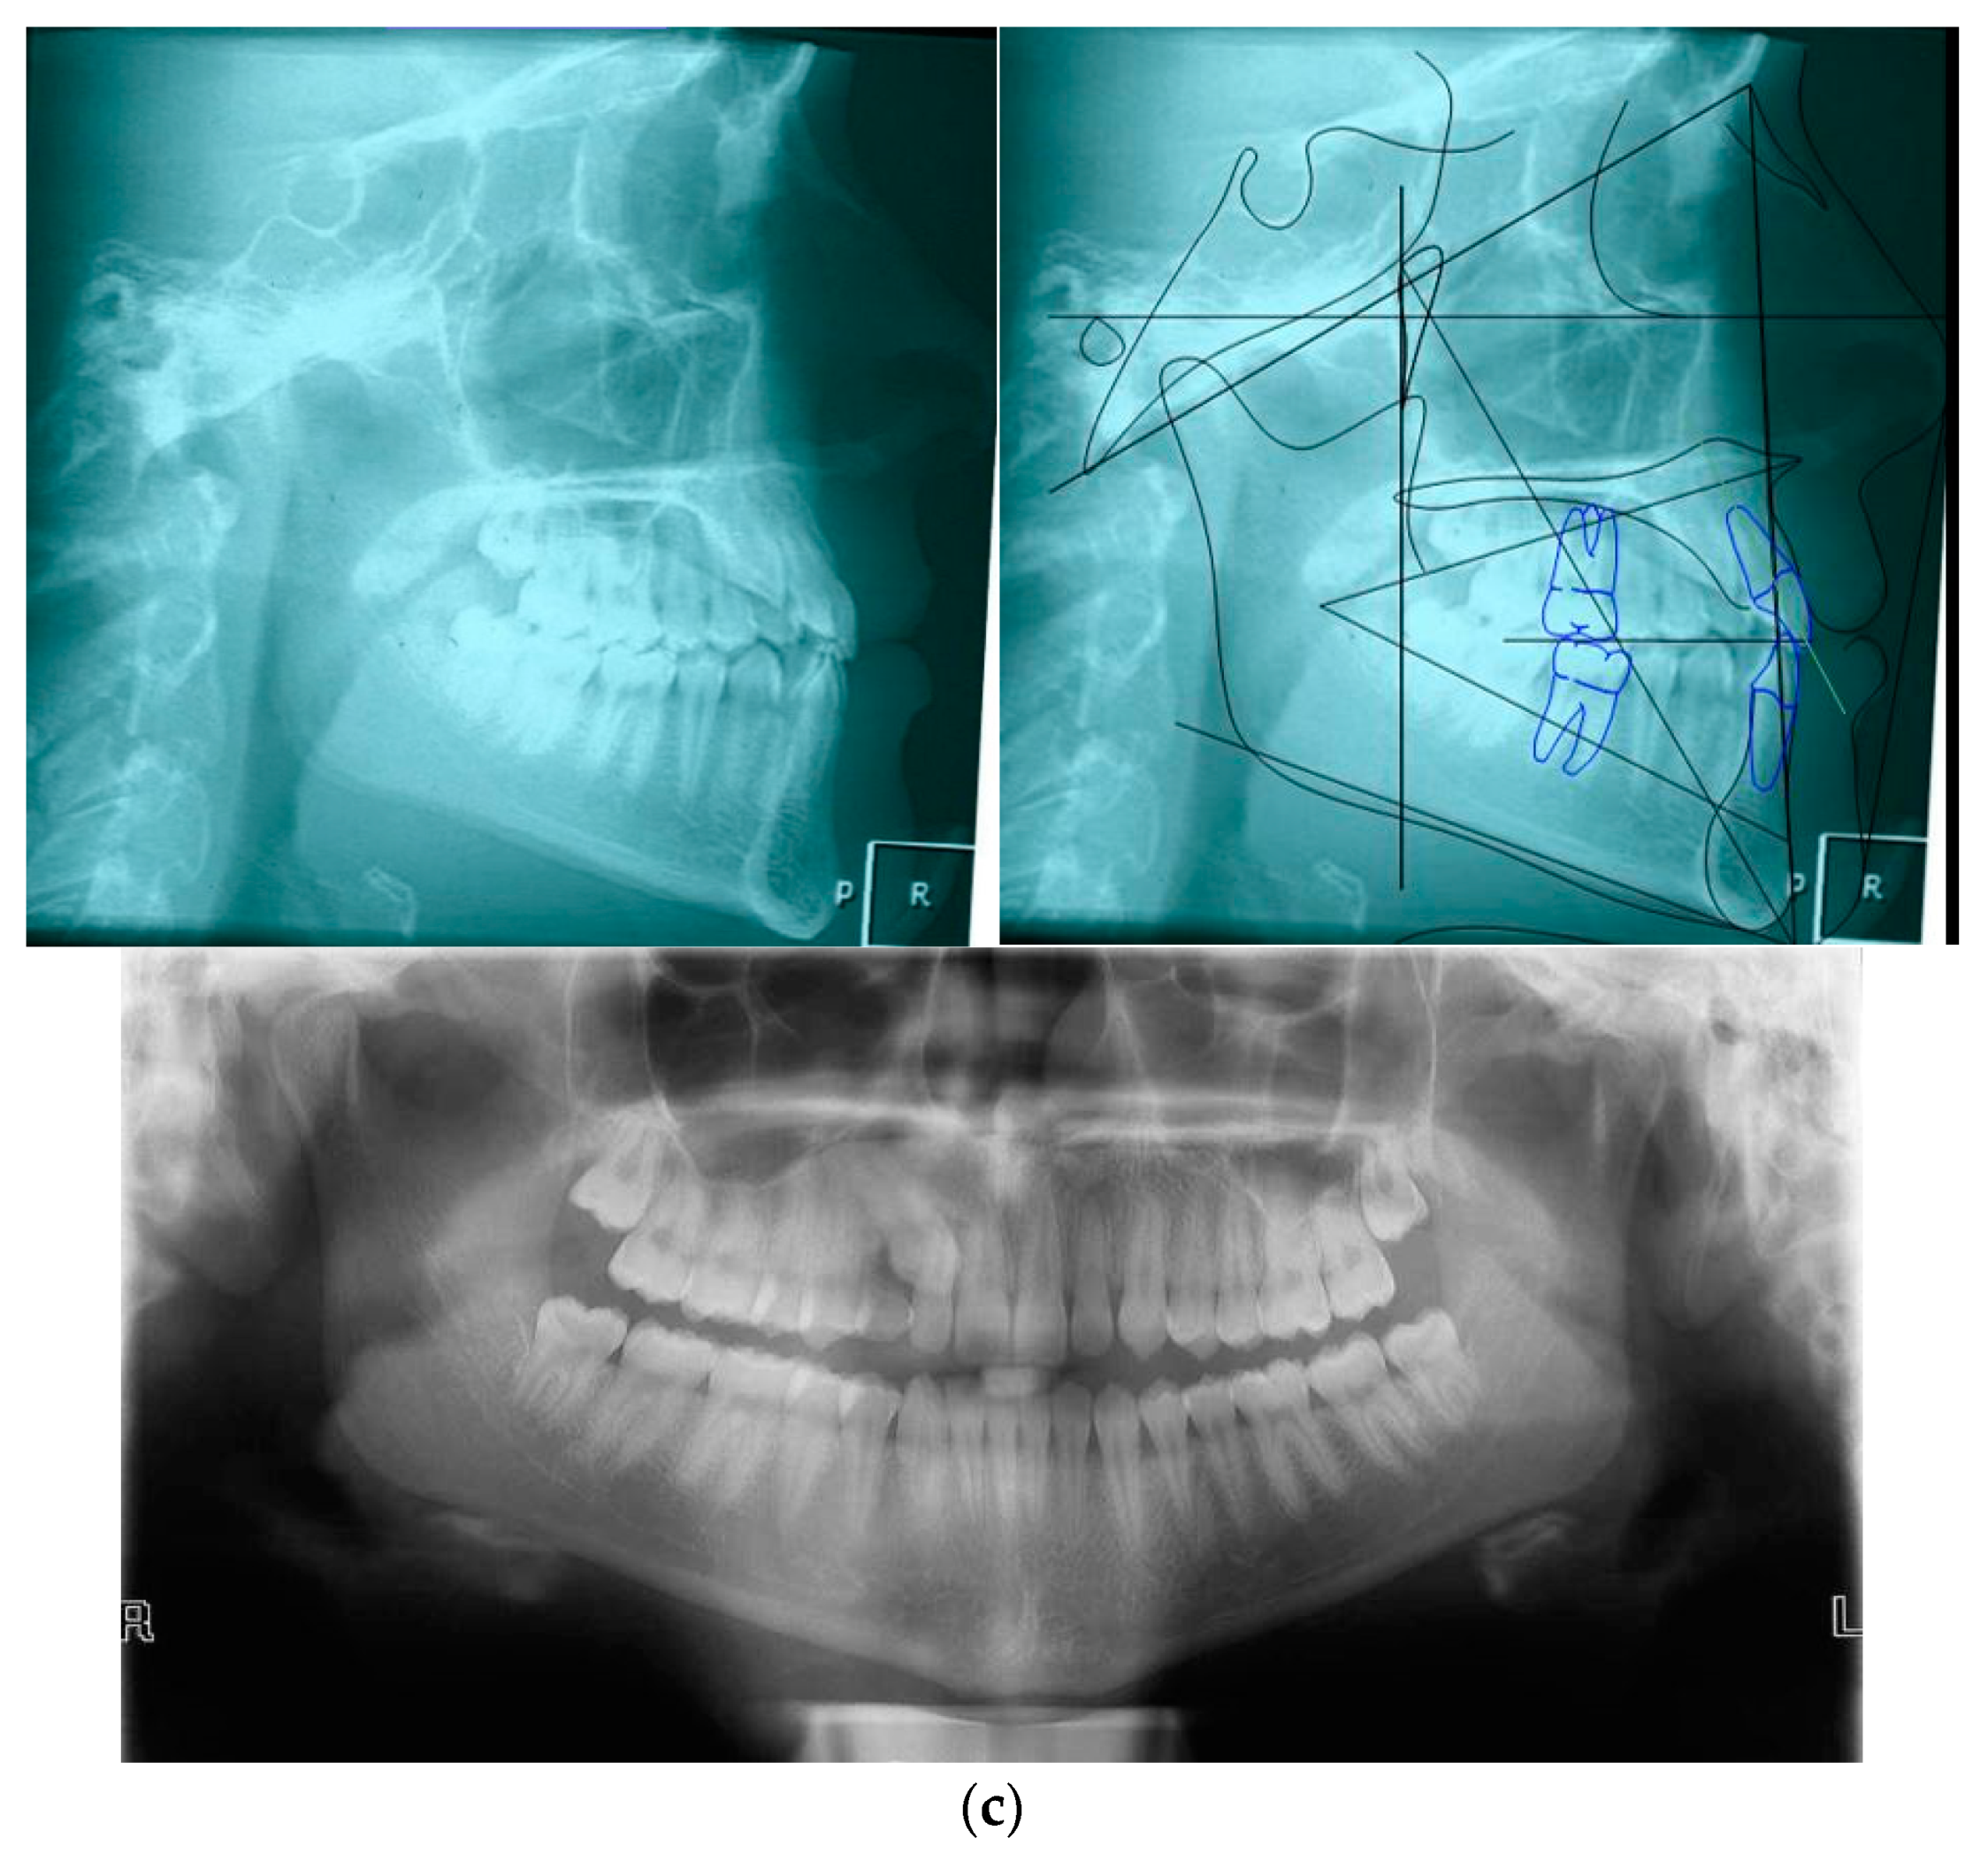

2.1. Clinical Case

| Sagittal Jaw Relationship | ||

|---|---|---|

| Patient Value | Normal Value | |

| Maxillary position SNA (°) | 81.4 | 82 ± 3.5 |

| Mandibular position SNB (°) | 81.8 | 80 ± 2.5 |

| Sagittal jaw relation ANPg (°) | −0.4 | 2 ± 2.5 |

| Vertical jaw relationship | ||

| Maxillary inclination SN^ANS-PNS (°) | 5.7 | 8 ± 3 |

| Mandibular inclination SN^GoGn (°) | 28.4 | 33 ± 2.5 |

| Vertical jaw relation ANS/PNS^GoGn (°) | 25.5 | 25 ± 6 |

| Dento-basal relationship | ||

| Maxillary incisor inclination U1^ANS-PNS (°) | 111.9 | 110 ± 6 |

| Mandibular incisor inclination L1^GoGn (°) | 81.8 | 94 ± 7 |

| Mandibular incisor compensation (L1-Apo) (mm) | 1.5 | 2 ± 2 |

| Dental relationship | ||

| Overjet (mm) | 2.9 | 3.5 ± 2.5 |

| Overbite (mm) | 2.1 | 2.5 ± 2.5 |

| Interincisal angle (°) | 143.5 | 132 ± 6 |